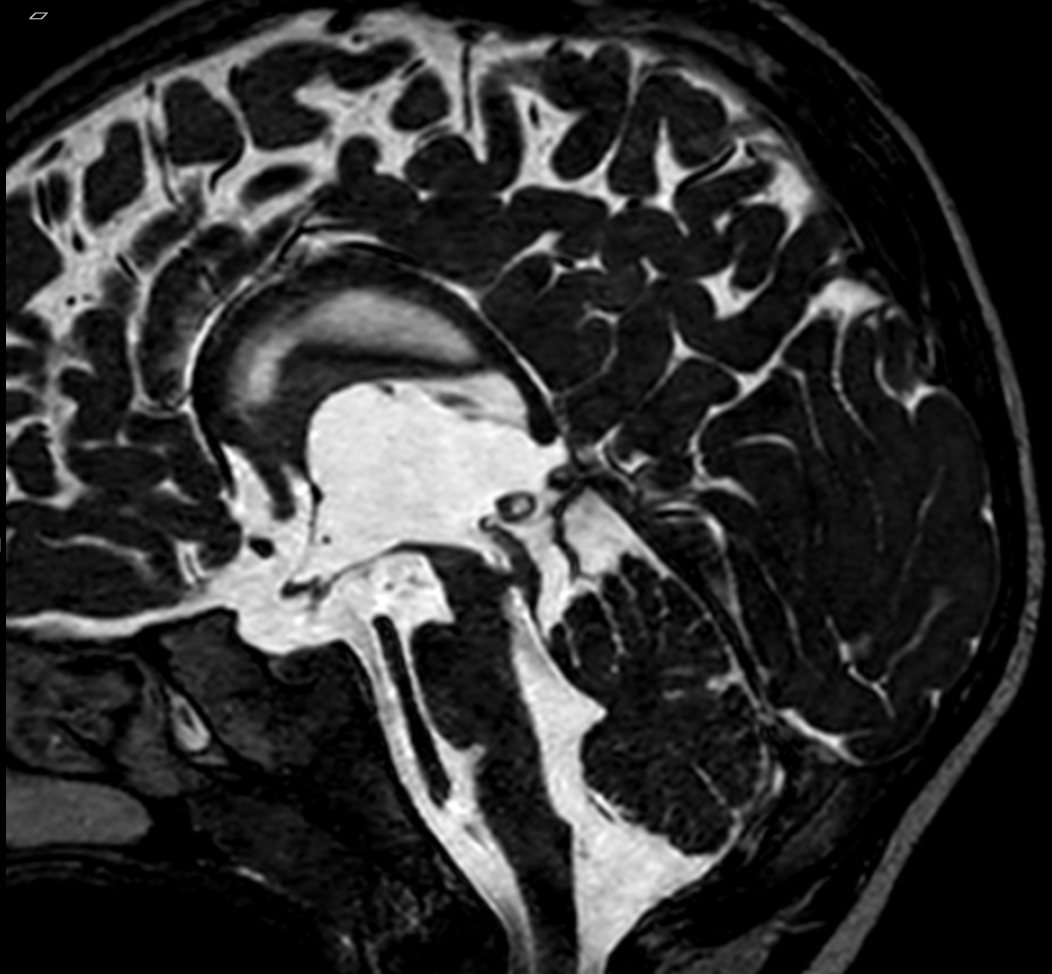

A sagittal T2-weighted MRI scan of a brain showing significantly enlarged, bright fluid-filled ventricles, characteristic of hydrocephalus.

CSF is continuously produced and absorbed at an equilibrium, maintaining a stable amount of intracranial fluid, which circulates around the brain and spinal cord. If production and reabsorption of CSF is not balanced, or there is an obstruction interfering with CSF flow, any slight difference may result in a build-up of CSF in the external and/or internal fluid spaces (ventricles) of the brain. This condition is called hydrocephalus.